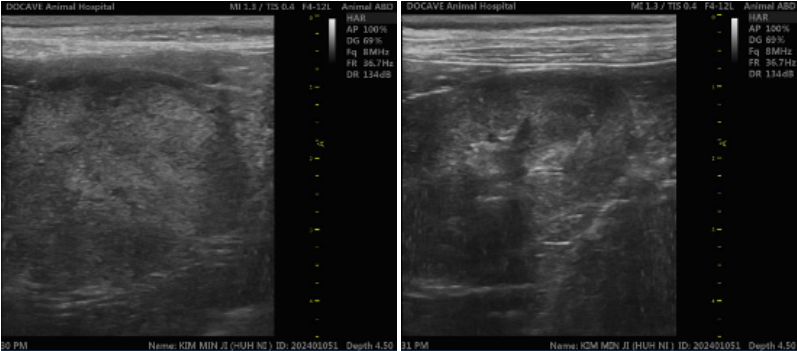

타원 강아지 비장 종양 의심 초음파 결과

01 비장종양 진단 – CT 검사